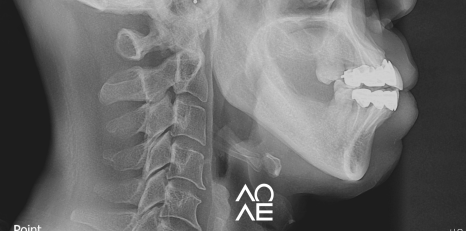

방사선 검사 등을 꼼꼼하게 진행해보니

교정이 아닌 크라운으로 치료가 가능한

구강 상태를 가지고 계셨기에 크라운 치료를

결정하고 진행하게 되었습니다.

| 치료 전(23. 12. 03) | 치료 후(24.06. 20) |